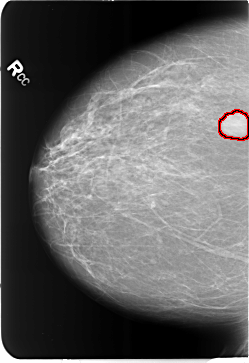

B_3484_1.RIGHT_CC

FILE: B_3484_1.RIGHT_CC.OVERLAY

TOTAL_ABNORMALITIES 1

ABNORMALITY 1

LESION_TYPE MASS SHAPE LOBULATED MARGINS CIRCUMSCRIBED

ASSESSMENT 4

SUBTLETY 5

PATHOLOGY BENIGN

TOTAL_OUTLINES 1

BOUNDARY